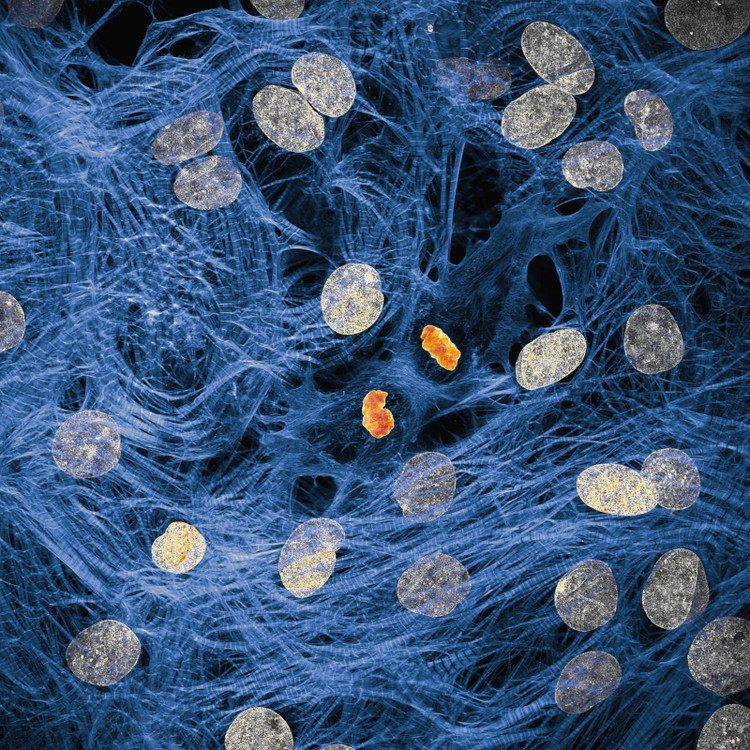

Anda tidak perlu menjadi pakar untuk mengetahui bahawa rangkaian sel di dalam badan kita bekerja keras untuk memastikan semuanya berjalan lancar. James Hayes dari Universiti Vanderbilt telah menangkap imej sel otot jantung dengan kromosom terkondensasi selepas pembahagian sel.